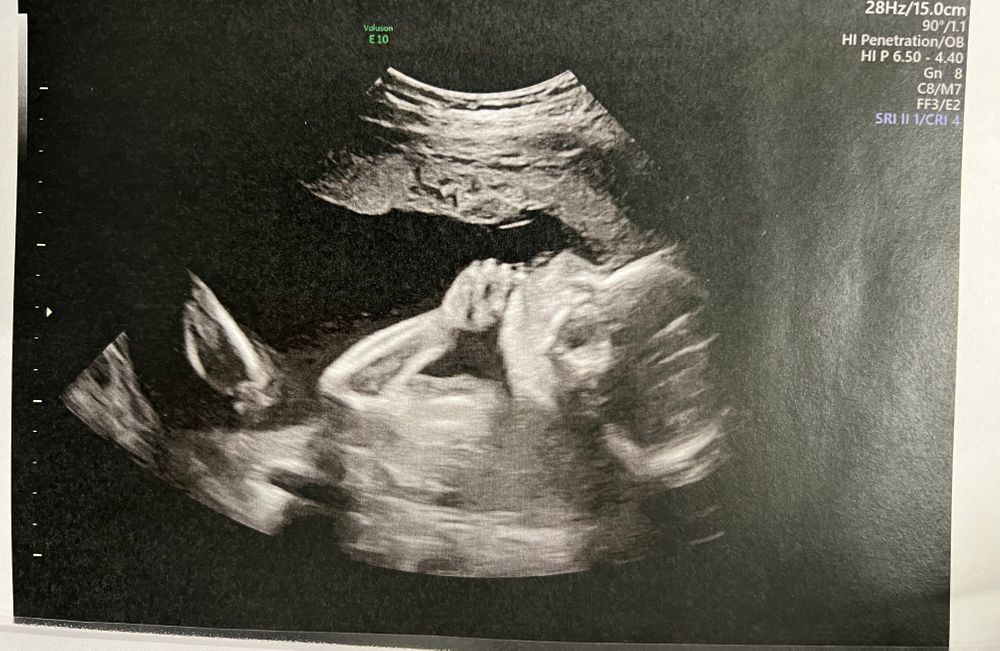

25 недель🤰🏼

- Гтт😋 сдала абсолютно нормально, после анализа приехала домой и просто отоспалась. Вечером уже чувствовала себя хорошо. Результат тоже пришел хороший. Больше боялась. После дозы глюкозы на узи было невозможно уловить человека. Выкрутасы были те еще. Лицом она так и не поворачивается. Продолжает сохранять интригу.

Вечно жующая свои пальцы мадам😌